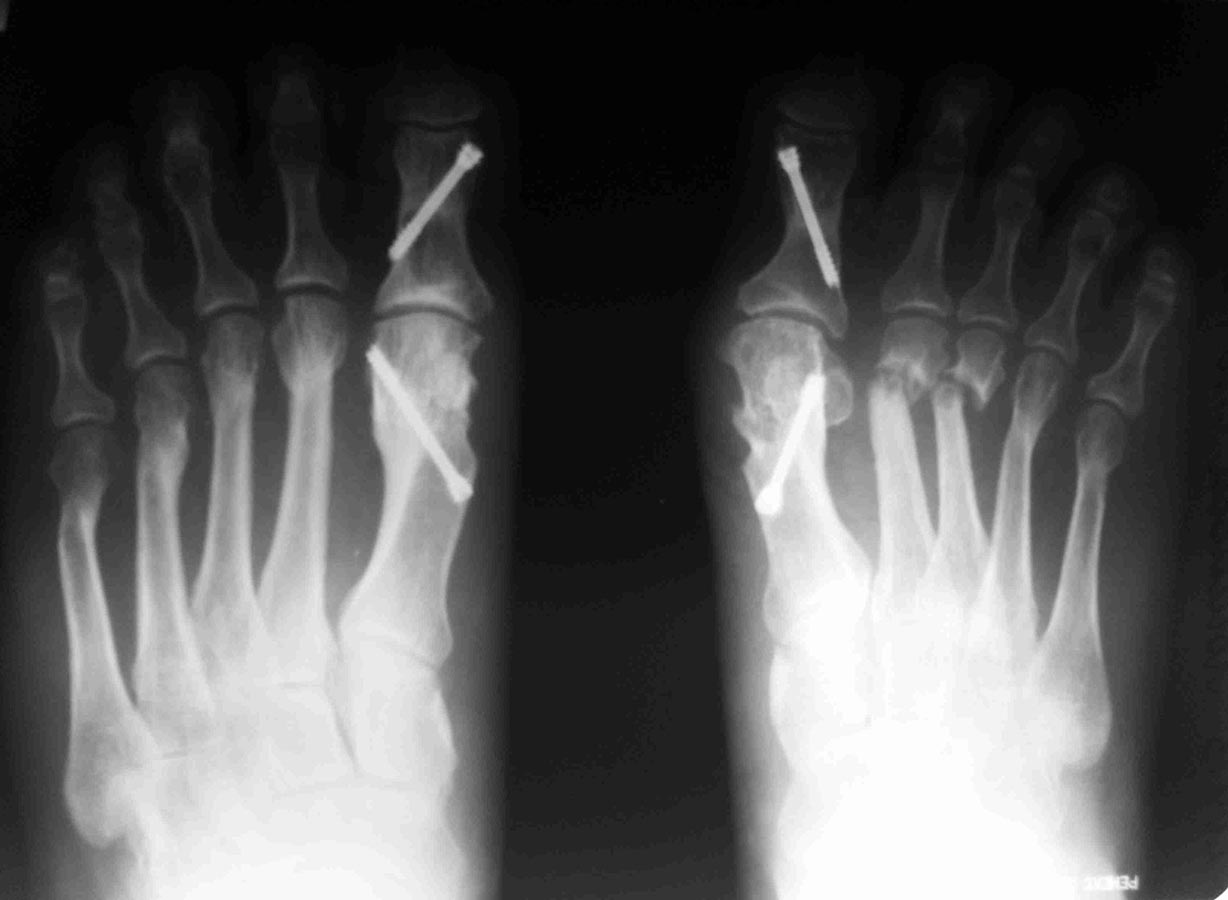

Уважаемые коллеги, я понимаю, что уже утомил вас оперированными стопами, но помогите еще с одним случаем Женщина около 50, активная, оперирована 1 год назад. Тип остеотомии в выписке не указан (похоже с 1-го по 5-ую + фаланги). Сожалею. что фото стопы не удалось выложить, клинически - выраженная девиация всех пальцев стопы слева. Что предпринять? Латеральный релиз, утягивание (лучшего синонима не нашел) медиальной капсулы+остеотомии 4-5 с нормальной повязкой? 1-ый луч - SERI (для жесткости остальных- к нему притянуть), но, головка и так скомпроментирована (или это не брать в расчет?)+ освежение ложняков+ коррегирующая остеотомия 4-5 Weil с фиксацией винтом (или без фиксации?). С фалангами что делать? Кажется, что ничего?

А чего Вы притесняетесь? Насчет "утомил вас оперированными стопами". Такая же ортопедия, как и вся остальная, обсуждаемая на форуме. Да еще сложный ревизионный случай. Изначально то все здорово было. Так бывает, к сожалению, когда все вроде правильно сделано, а в результате не складывается. Почему-то 2 из 10 плюсневых не срослись. На прошлогодней конференции AOFAS был доклад о неудачах после операций на стопе, в котором авторы выделили группу «нестрастальщиков»: пациентов, которые не срастаются без очевидных причин для этого. Может и здесь подобный случай. Из предложенного Вами плана не ясно, зачем делать SERI? Ее ведь сделали год назад. Только не стандартный вариант с фиксацией спицей, а более сложный, с внутренней фиксацией. Возможно, в этом была причина избыточной латерализации головок: подошвенные пластинки 1 и 2 плюснефаланговых суставов тесно связаны. Слишком радикальное уменьшение первого межплюсневого угла за счет латерального смещения головки первой плюсневой привело к дестабилизации нефиксированных остеотомий 2 и 3 плюсневых. И если сейчас еще больше переместить головку первой плюсневой кнаружи, это только усугубит ситуацию. На схеме я показал, в каком положении окажутся 2 и 3 пальцы в случае репозиции головок их плюсневых: расстояния между 1 и 2 лучами итак практически не остается. Я бы в данном случае подровнял внутренний контур головки 1 плюсневой, удалил винт из основной фаланги, выполнил латеральный релиз 1 плюснефалангового, эйкиноподобную остеотомию основной фаланги 1 пальца; репозицию головок 2-3 плюсневых с фиксацией их головок спицами на 4-6 недель и положив в область ложных суставов костную аутостружку или какой-нибудь искусственный заменитель кости. Если при этом пальцы не станут ровнее – выполнил бы остеотомии основных фаланг соответствующих пальцев. Без вмешательства на 4-5 плюсневых.